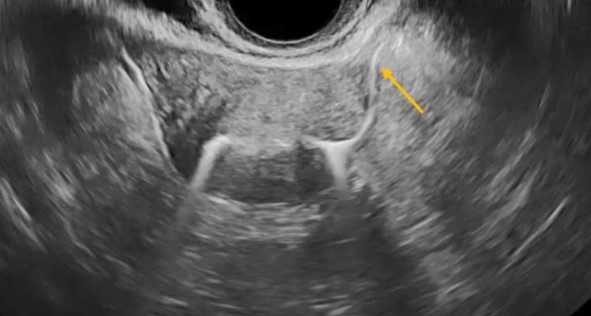

Παράδειγμα υπερηχογραφικής σαλπιγγογραφίας : Διμερής διαπερατότητα HYFOSY με ExEm® Foam – φαίνεται καθαρά η ροή από την αριστερή σάλπιγγα (κίτρινο βέλος: έντονο λευκό σήμα σκιαγραφικού).